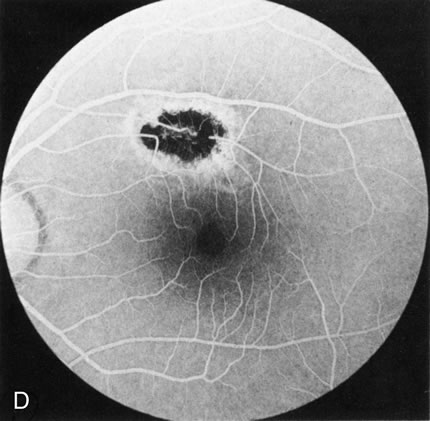

In Stargardt's disease, thes most common hereditary macular dystrophy, FA has a variety of functions. In the mildest fundus presentation, with visual symptoms and visual function out of proportion to the observed maculopathy, FA can confirm or even make the diagnosis and can avoid a mistaken diagnosis of malingering, hysteria, or central nervous system disease (Fig. 9A and B). When a maculopathy is present without surrounding parafoval flecks, FA may show patchy areas of transmission hyperfluorescence in the posterior pole, indicating a more diffuse involvement (Fig. 9C and D).

Fig. 9. Stargardt's disease–fundus flavimaculatus. The mild maculopathy (without parafoveal flecks) (A) is confirmed by the angiogram (B). The relative absence of the underlying choroidal flush, resulting in an easier visualization of the overlying retinal capillary circulation, has been referred to as the “silent” or “dark” choroid, and is considered a common finding in this disease. The diagnosis is confirmed in an individual with a pigmentary maculopathy without flecks (C). Here the angiogram demonstrates widespread transmission hyperfluorescence and a “silent” or “dark” peripapillary area (D). When the posterior pole shows multiple yellowish-white flecks (E), the angiographic findings do not necessarily correspond to the flecks (F). It should also be noted that despite the widespread abnormalities, the background choroidal fluorescence is normal.

In a large majority of patients (86% in one study),20 there is an absence or decrease in the background choroidal fluorescence (which is referred to as the “silent” or “dark” choroid) (see Fig. 9B). This warrants special attention because it occurs so frequently, is rarely found in other retinal disorders,21 and may be related to histopathology that shows an increase in lipofuscin in the RPE.22